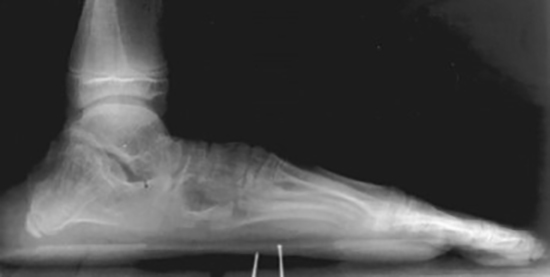

flat foot of patient with Marfan syndrome

X-ray shows the narrow, flat foot of a patient with Marfan syndrome.

Reproduced with permission from Fitzgerald RH Jr (ed): Orthopaedic Knowledge Update 2. Rosemont, IL. American Academy of Othopaedic Surgeons, 1987, pp. 9-17.